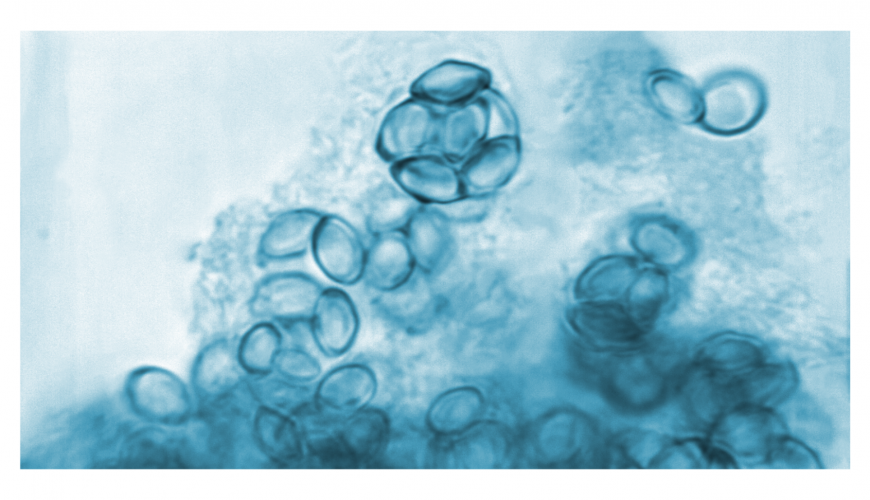

Sporotrichosis

It is an emerging fungal zoonosis caused by pathogenic fungi belonging to genus Sporothrix . Generally, most species from this genus are non-pathogenic environmental fungi present in soil, woods and decaying matter. However, some species like Sporothrix schenckii, S. brasiliensis, S. globosa, and S. luriei, cause disease in humans and animals. Human infection may occur through direct inoculation of fungal spores into skin and mucosa from environment. Zoonotic risk is more in case of S. brasiliensis and cat to cat, cat to dogs and cat to human transmission is possible. Cat-transmitted sporotrichosis has been documented in isolated cases or in small outbreaks in American and Asian continents. Incidence of cat-associated sporotrichosis is very high in Brazil, and Rio de Janeiro is considered as hyperendemic region for sporotrichosis.